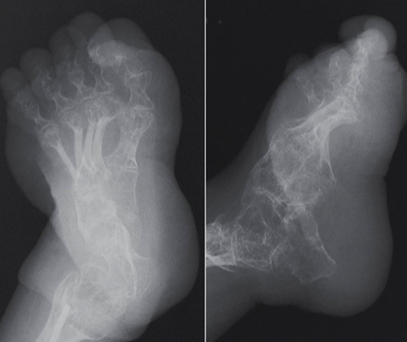

Radiographic Appearance - Osteogenesis Imperfecta

osteoporotic bones, thin cortices

callus formation

widened sutures, multiple wormian bone